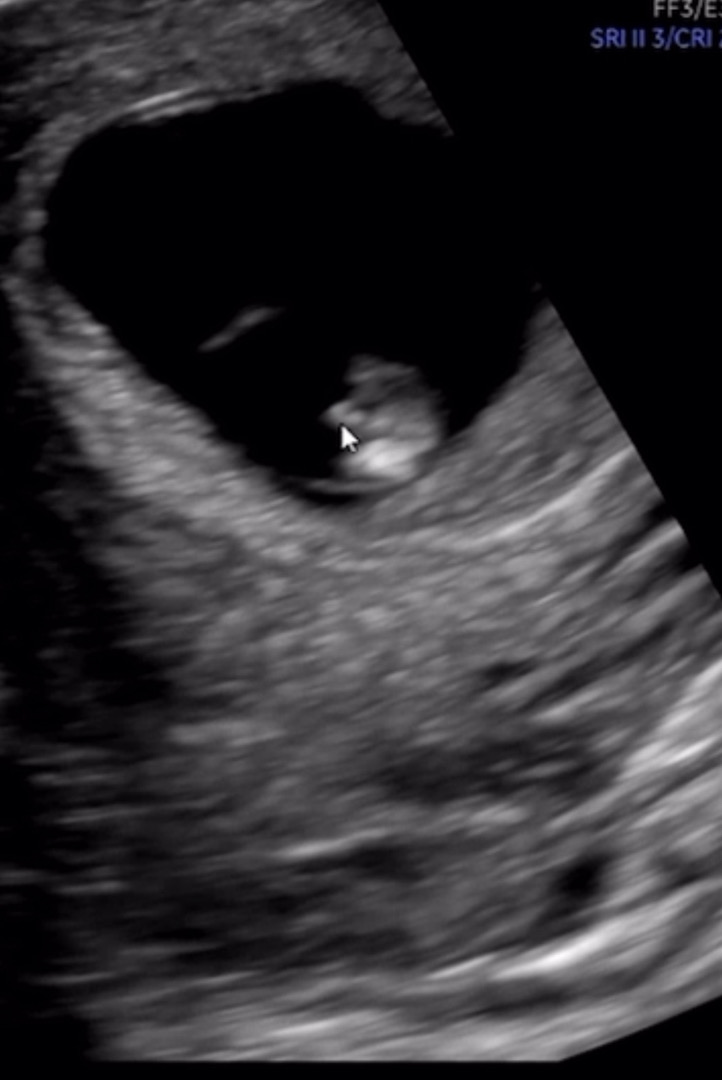

아들인거같다는데 성별반전 가능성이 있을까요?

11주차 엉덩이쪽을 찍었는데 뭔가가 저렇게 튀어나와있네요..! 의사쌤은 아들같지만 아직 지켜보자하시는데 저정도면 아들확정인건지 아니면 성별 반전 가능성이 있울까요~? ㅎㅎ

제 친구 아기가 12주차에 볼록 튀어나온 것 때문에 아들인것 같다 예상했는데요, 16주차에 딸로 바뀌었어요! ㅋㅋ

딸>아들은 잘 바뀌는데 아들>딸은 잘 안바뀐대요!

맞아요 ㅎㅎ 아들은 처음부터 보이면 그냥 아들이에요~ 아들 키우기 재미있어요~😁

11주면 아직 몰라요ㅎㅎ 반전가능성 있어용